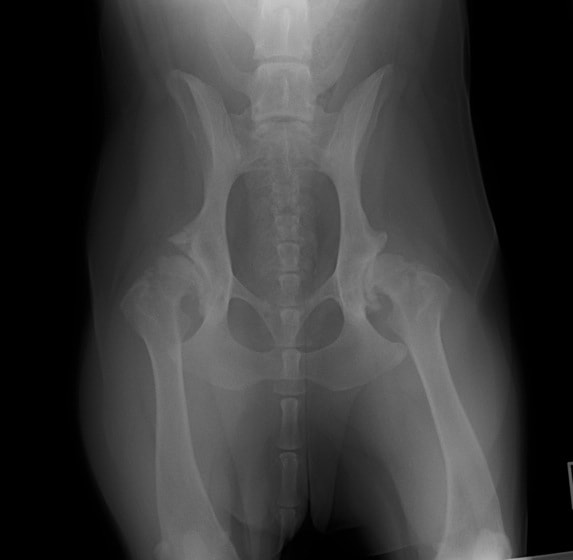

重度股関節形成不全の症例

ボール遊びの後の後肢の跛行を主訴に来院されました。院内ではモンローウォーク(腰を振って歩く歩様)が認められました。レントゲン検査において、左右股関節の形成不全および比較的重度の関節炎所見を認めました。左右ともに長期に及ぶ骨関節炎の進行により、寛骨臼に重度の骨変形・骨硬化が認められました。このような症例においては、THRのカップの定着が悪くTHRの手術の成功率が下がるため、機能回復の面では劣りますが、症状がより重く、筋肉の萎縮の認められた右後肢の大腿骨頭・骨頚切除術を実施しました。関節面に関節軟骨の欠損、骨増殖体を認めました。今後は、リハビリテーションを行い、患肢の機能回復に努め、反対側の大腿骨頭・骨頚切除術を検討していく予定です。

術前レントゲン

後肢の跛行を主訴に来院されました。レントゲン検査にて、左右股関節の形成不全および重度の関節炎所見を認めました。THRに関しては適応年齢(約9カ月齢以降)の範囲にありますが、左右とも長期に及ぶ骨関節炎の進行により、大腿骨頭・寛骨臼ともに重度の骨変形を伴っていました。このような症例において、THRのカップの定着が悪くTHRの手術の成功率が下がるため、機能回復の面では劣りますが、症状がより重いと判断された左後肢の大腿骨頭・骨頚切除術を実施しました。今後は、リハビリテーションを行い、患肢の機能回復に努めると共に、反対側の大腿骨頭・骨頚切除術を検討していく予定です。